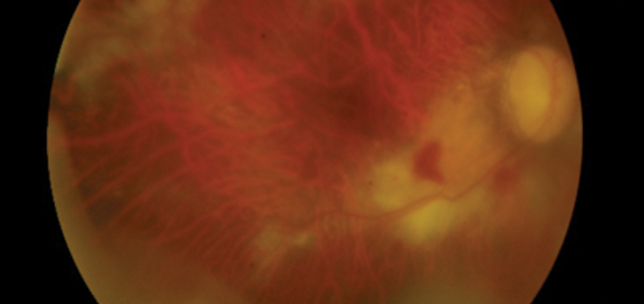

An unusual case of acute retinal necrosis

Pouya Alaghband

,

Louise Downey

Seema Arora

1st August 2015

Education

Case Reports